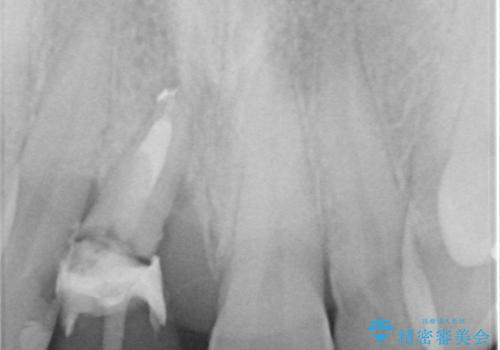

磨き残しなどによるプラークの付着が多いため、仮歯の用意と手術アポイントの調整を行っている間に口腔内のクリーニングなどを施し、環境がある程度改善されたのちに、抜歯即時インプラント埋入、即時荷重(インプラント埋入時に仮歯の装着)の予定で治療を行うこととしました。

度重なる脱離により、表側の炎症が非常に強くなっており、歯を支える骨が失われている状態でした。

そのため、現在の位置よりも歯と歯肉の位置が退縮する方向に移動する可能性があり、前歯2本の歯肉位置が大きくずれることとなるため、本人との相談のうえ、天然歯が萌えているような歯肉状態とはならないものの、2本の段差が少ない状態にて治療を終えることとなりました。